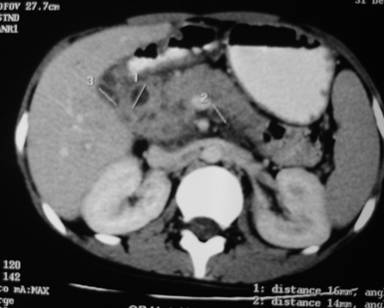

A 15-year-old woman presented with complaints of continuous upper abdominal pain for the past 25 days with occasional radiation to the back. The pain was severe in nature and she had to take analgesics regularly. The pain was unrelated to meals. Other symptoms were anorexia, 7.3 kg weight loss, and low-grade fever at night. The patient did not have jaundice or gastrointestinal bleeding. There was no past history of tuberculosis of the patient or her close relatives. Physical examination revealed pallor and a fixed, mildly tender, irregular surfaced mass at the epigastric region. Investigations showed hemoglobin of 7.3 g/dL (reference range: 13.2-16.2 g/dL), total leukocyte count of 8,600 mL-1 (reference range: 4,000-11,000 mL-1) with a normal differential count, erythrocyte sedimentation rate of 102 mm/first hour (reference range: 0-17mm/first hour). Liver function tests were normal. Results of HIV serology were negative, and results of chest radiograph were normal. A CECT abdomen (Figure 3) showed heterogeneously enhanced pancreatic head mass with multiple enlarged peripancreatic lymph nodes with central necrosis. EUS-guided FNA (using Echotip 22G, Wilson Cook needle, Salem, NY, USA) from the peripancreatic lymph nodes showed epithelioid cell granuloma and caseation necrosis (Figure 4) but Ziehl-Neelsen stain failed to reveal any acid fast bacillus. We started antituberculous drugs and the patient improved dramatically within 2 weeks. Antituberculous therapy was continued for 6 months. After 30 months of follow-up she was pain free, gained 12.7 kg weight, and the mass was no longer visible at a follow-up CT scan of the abdomen.

Figure 3. CECT abdomen showing pancreatic head mass with necrosed peripancreatic lymph nodes (Case #2). |